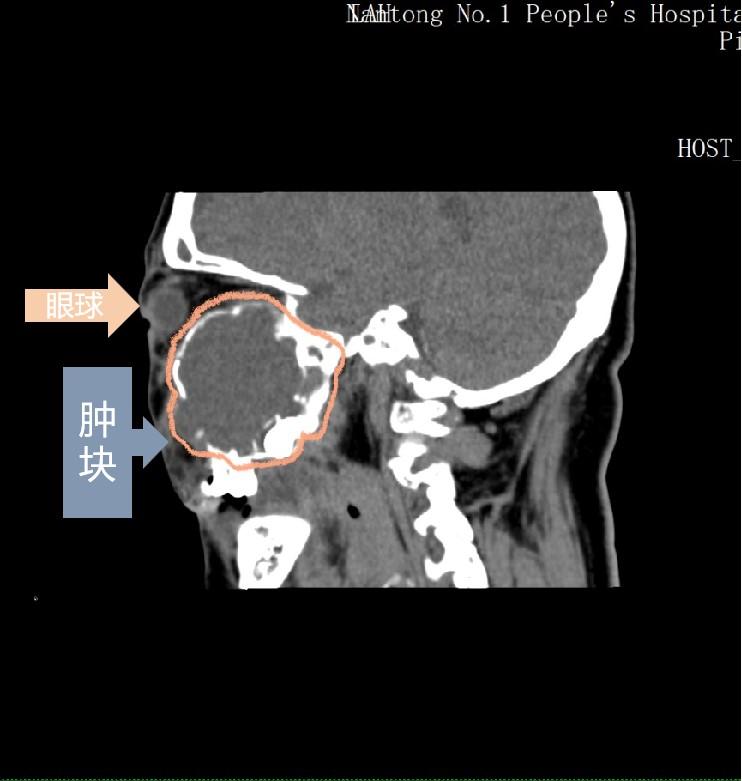

△患者CT图像

根据陈阿姨的眼部CT和磁共振检查,王勇发现该患者右眶、鼻腔内肿块达5厘米*5.2厘米(相当于鸡蛋大小),右眼球已被挤到外上方,肿块向上已经压迫吸收前颅底骨质,与大脑仅仅相隔一层薄薄的软组织,并且向后压迫视神经。